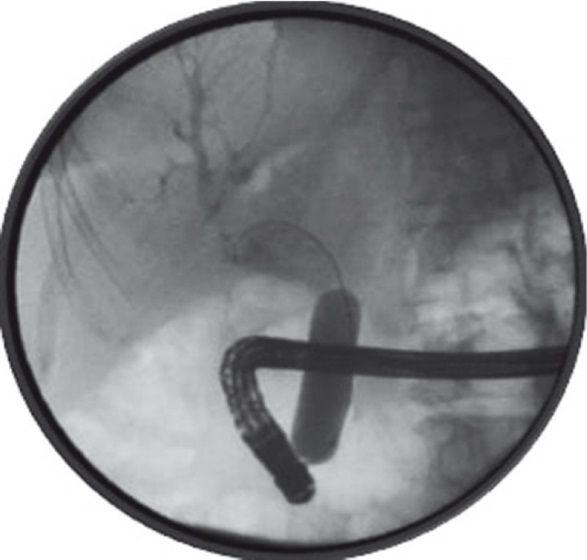

После удаления стента выполнена дилатация протока баллоном 18 мм (рис. 1), но добиться изменения положения конкремента не удалось.

Рисунок 1 [1].